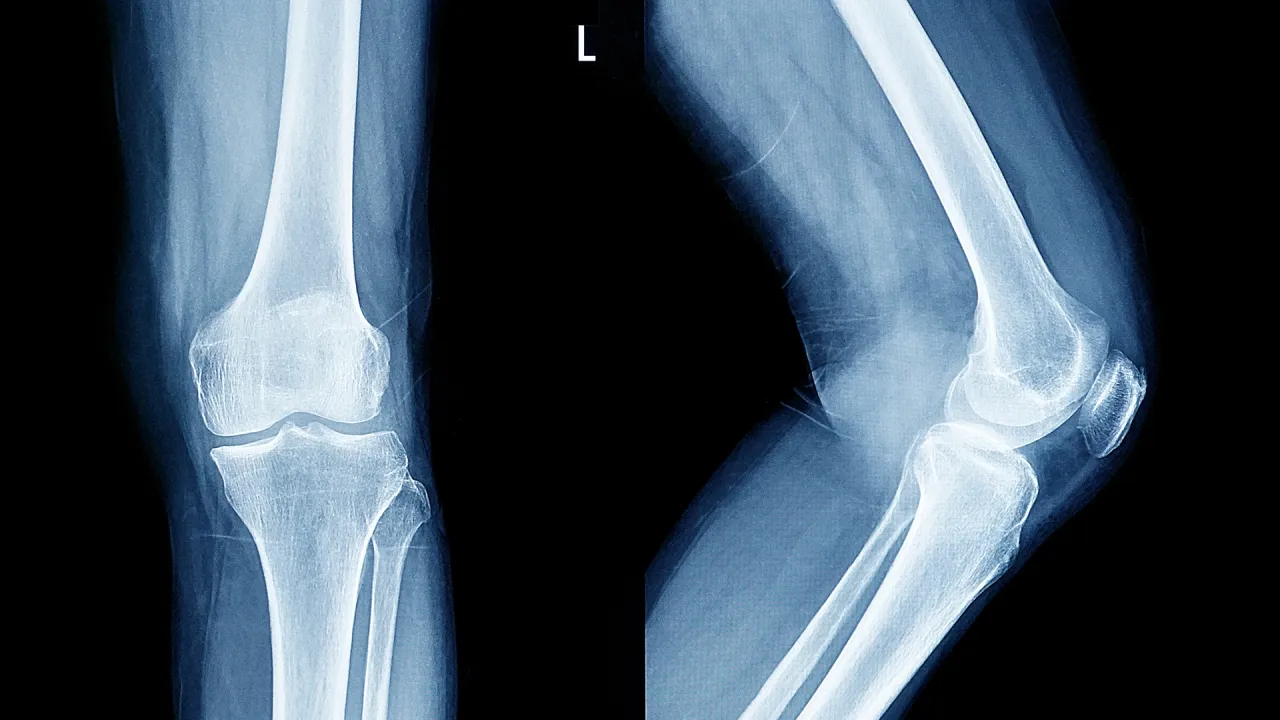

عالمة تحدد مرحلة عمرية حرجة تبدأ فيها العظام بفقدان صلابتها

قالت هاسميك جاسمين سامفيليان، المحاضرة الأولى في الطب الحيوي بجامعة أنجليا روسكين البريطانية، إن العظام تبدأ بفقدان صلابتها تدريجيا لدى معظم الناس بعد سن 25-30.

ووفقا لها، تبقى عمليات تفتت العظام وتجديدها متوازنة لدى الشباب. وعادة ما تبلغ كتلة العظام ذروتها بين سن 25 و30 عاما، وبعد ذلك يصبح تدمير العظام أكثر شيوعا بشكل تدريجي، مما يؤدي إلى انخفاض كثافة العظام مع مرور الوقت.

ويُعدّ التقدم في السن عامل الخطر الرئيسي، لكن هناك عددا من العوامل الإضافية التي قد تُسرّع هذه العملية. وتلعب التغيرات الهرمونية، على وجه الخصوص، دورا هاما. إذ يؤدي انخفاض مستويات هرمون الإستروجين بعد انقطاع الطمث إلى زيادة فقدان العظام، مما يُسبب كسورا لدى ما يقرب من نصف النساء فوق سن الخمسين.

وقالت الخبيرة: "نمط الحياة لا يقل أهمية. فالتدخين وإدمان الكحول وقلة النشاط البدني تساهم في ضعف العظام. كما يلعب النظام الغذائي دورا مهما: فنقص الكالسيوم وفيتامين د يقلل من قدرة الجسم على الحفاظ على قوة العظام".

وتوجد مخاطر إضافية مرتبطة ببعض الحالات الطبية والأدوية. وعلى وجه الخصوص، فإن الاستخدام طويل الأمد للستيرويدات والأمراض التي تؤثر على امتصاص العناصر الغذائية يمكن أن تسرع من فقدان العظام لصلابتها.